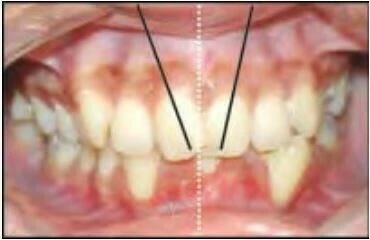

1.7 RĂNG XOAY

Đây là tình trạng những răng di chuyển xung quanh trục dọc của nó. Có hai kiểu xoay răng:

Gần trong hoặc xa ngoài

Mặt gần của răng nghiêng vào trong, hay nói cách khác mặt xa của thân răng nằm về phía ngoài so với mặt gần.

Xa trong hoặc gần ngoài

Mặt xa của răng nghiêng vào trong, hay nói cách khác mặt gần của thân răng nằm về phía ngoài so với mặt xa của nó.